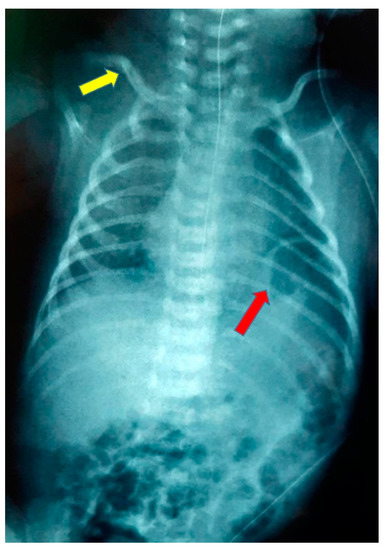

The abdominal ultrasound performed 1 month later was without pathological findings. The chest/abdominal X-rays at the age of 3 and 6 months were normal, and there were no signs indicating a rebound of the eventration of the diaphragm (Figure 4). The right brachial plexus paresis was resolved at the age of 6 months. The infant had adequate growth, and no feeding problems were reported from the parents.

Figure 4. Chest radiograph at the age of 3 months.